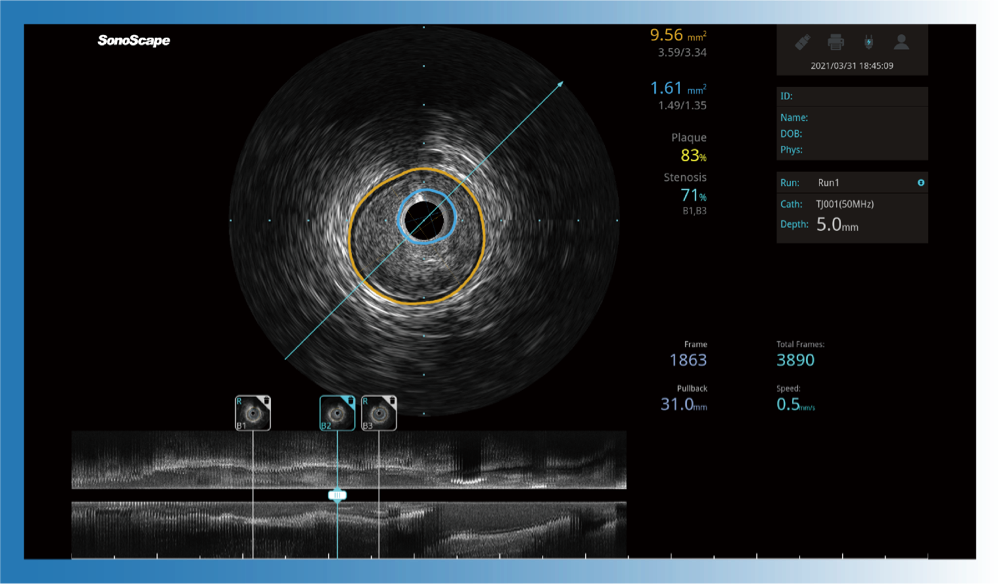

智能自動描跡和定量分析

一鍵智能描跡,自動測量斑塊負(fù)荷、面積狹窄率等指標(biāo),準(zhǔn)確率高于90%